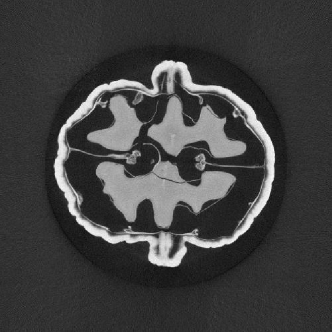

In Fig. 4, a comparison of the central slice of volumes reconstructed with different redundancy weights is presented. The results show that the neural network, after training, can achieve reconstruction results similar to those obtained through analytical methods.

Refer to caption

(a)

(b)

(c)

Figure 4: Reconstructed results of the network. (a) Reconstruction using learned redundancy weight. (b) Reconstruction using analytic redundancy weight. (c) FDK reconstruction result.